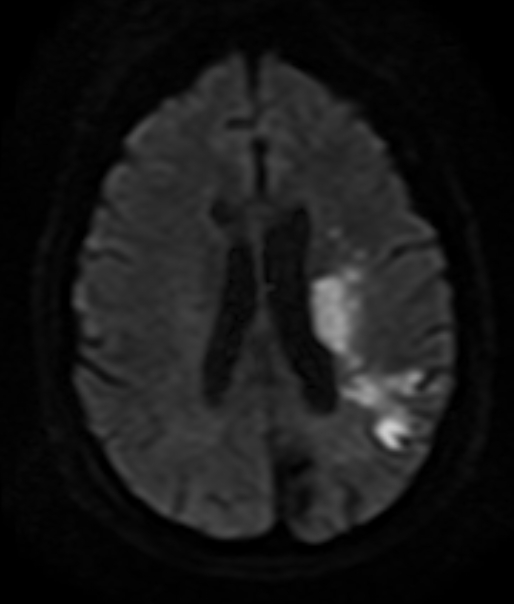

ECG shows normal sinus rhythm. MRI of the brain reveals multiple acute cortical and subcortical infarcts in the left middle cerebral artery territory, as shown in the image below. CT angiography of the head and neck reveals 80%-90% stenosis at the origin of the left internal carotid artery. Echocardiogram shows mild left atrial enlargement, left ventricular hypertrophy, and left ventricular ejection fraction of 65%. The patient receives low-dose aspirin in the emergency department.